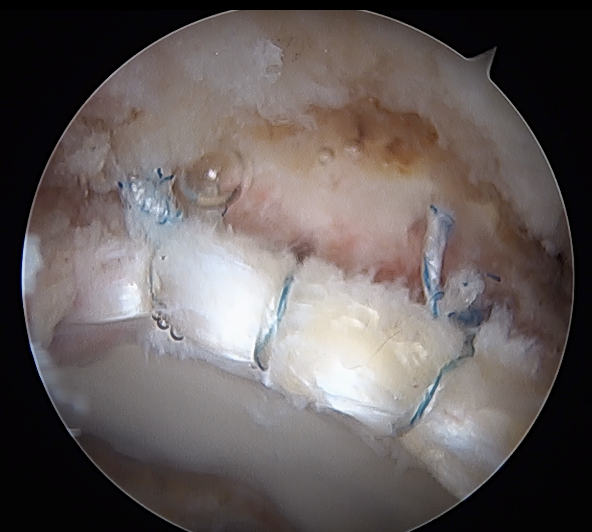

Labral repair

Options

- knotted versus knotless anchors

- straight versus curved

Must avoid intra-articular penetration

Capsular Repair

T capsule closure

Interportal capsule closure